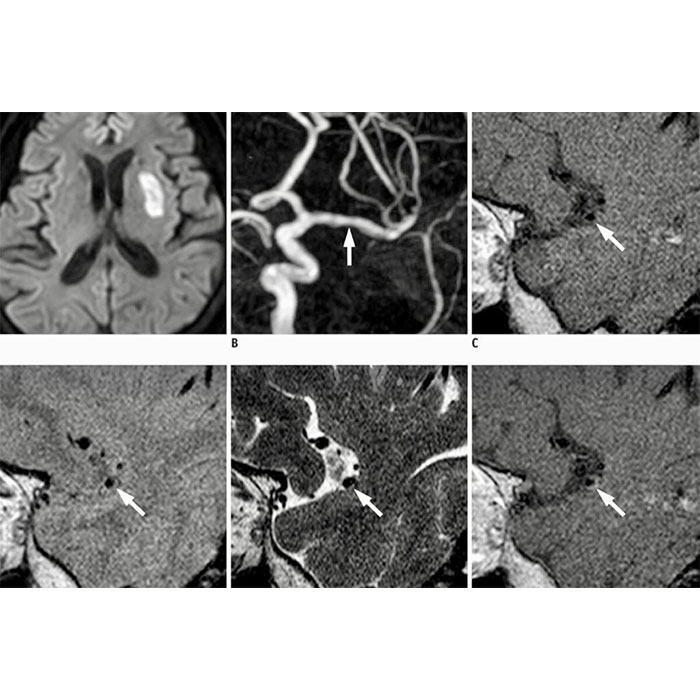

Renkli Doppler ultrasonografi, BT ve MR anjiografi, DSA başlıcalarıdır. Bu modalitelerden sadece DSA için özel işlem gerekmektedir. Bu işlemin uygulanabilmesi adına güvenilir ve steril bir ortam yeterli olmaktadır. Mevcut kriterlere sahip merkezlerde kolaylıkla uygulanabilecek olan mevcut işlemlerde, kişilerin rahatsızlığına yönelik tanı ve tedavisi için tüm hizmetler sunulmaktadır.

Damar ile ilgilenen en alt branşlardan birisi olan vasküler radyolojisi, damarda yaşanabilecek pek çok farklı problemin etkin bir şekilde tedavi edilmesini sağlar. Bu bakımdan tedaviler pek çok farkı rahatsızlığın giderilmesinde etkili olmaktadır. Temel olarak amaçlanan damarın açılması, kapatılması, kanamaya neden olan damarların tespit edilmesi ve dolaşım sisteminde yer alan çeşitli rahatsızlıkların tanı ve tedavisinin sunulabilmesidir. Mevcut alanda, sunulan tedavilerde öne çıkanlar ise şöyledir;